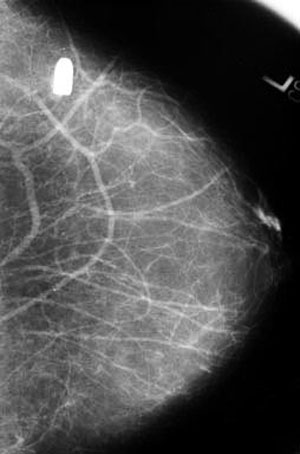

6. Viên đạn nhỏ bằng hạt đậu nằm trong ngực trái người phụ nữ này nhiều năm nay sau khi cô bị bắn. Nó dường như không gây bất kỳ ảnh hưởng nào đối với sức khỏe cho tới khi cô đi chụp X-quang: